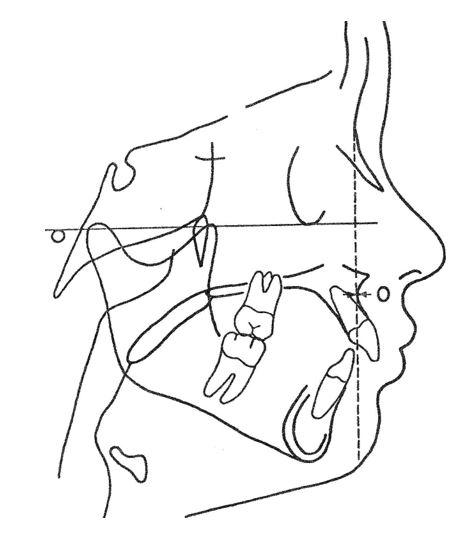

1. “Ulf Posselt’s Envelope of Motion 1952 (Envelope of Function (Border Movement)) was developed before the availability of Dental cone beam computed tomography (CBCT). It can describe the mandibular movement in relation to the maxilla. The various mandibular movement points can be updated to meet today’s added information.” (See Figure 1.)

RCP = Retruded contact position.

ICP = Intercuspal position.

RCP – ICP = This path is termed a slide. It has the potential for horizontal, vertical, and lateral components. The lateral element to this slide cannot be seen in the sagittal plane. (Condyle movement within Ricketts’ A position). (If there is no Ricketts’ A position, the Movement will be limited) or (with disc damage or displacement).

E = Edge-to-edge position of incisors.

Pr = Maximum protrusion.

R = Maximal mandibular opening with the condyle in the most Retruded position.

(R will vary depending on Ricketts’ A position) (If there is disc displacement and no tm joint space, the Maximum Opening will be limited.)

T = Maximal mandibular opening with full anterior-inferior translation of the condylar head.

Ulf Posselt’s Envelope of Motion can have two possible border

movements based on whether there is Ricketts’ A position or no Ricketts’ A position.

For example:

1. RCP = With a healthy T.M. Joint complex and the disc supported in Ricketts’ A Position, the disc will support the terminal hinge axis rotation and translation without disc displacement. The mandible can open to the T position. (See Figure 2.)

With an unhealthy T.M. Joint complex, the disc is not supported in Ricketts’ A Position. During the terminal hinge axis rotation and translation, disc displacement can happen. The condyle can be pushed posteriorly and superiorly with or without popping noise. “If an adequate disc position does not support the occlusion, the surgical procedure will fail.” 8

RCP – ICP slide may be no more than the condyle moving within the tm joint space (Ricketts’ A Position). (Figure 3.)

Figure 1: Ulf Posselt’s Envelope of Motion 1952 (Envelope of Function (Border Movement)

Figure 2: T opening in Ricketts’ A Position w disc support

Figure 3: Opening in Ricketts’ A Position w disc support